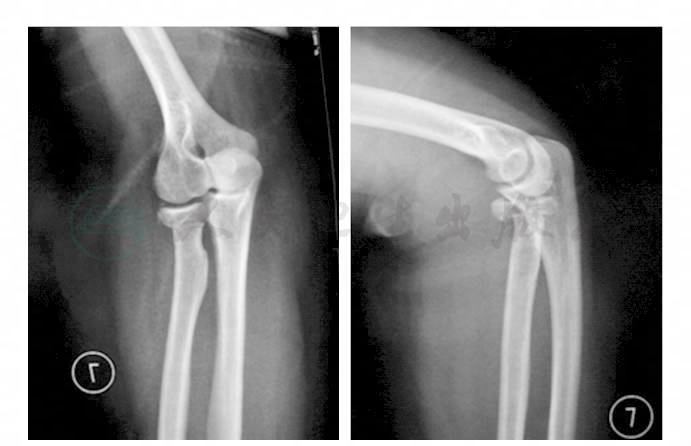

术后第2日,嘱患者开始患侧肘的被动活动,术后第3日移除引流管,行X线检查示钢板位置良好,无松动、断裂(图2),术后第5日开始肘关节各个方向的主动活动,包括屈伸及旋前、旋后。

图2 术后肘关节正侧位X线片